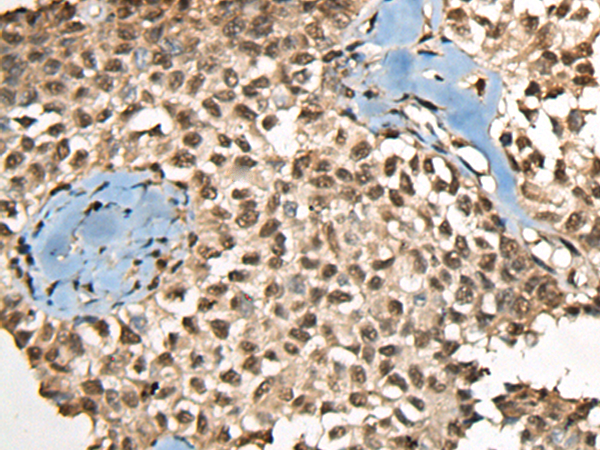

IHC (Immunohistochemistry)

(The image on the left is immunohistochemistry of paraffin-embedded Human thyroid cancer tissue using 46418(CCDC12 Antibody) at dilution 1/60, on the right is treated with fusion protein. (Original magnification: x200))